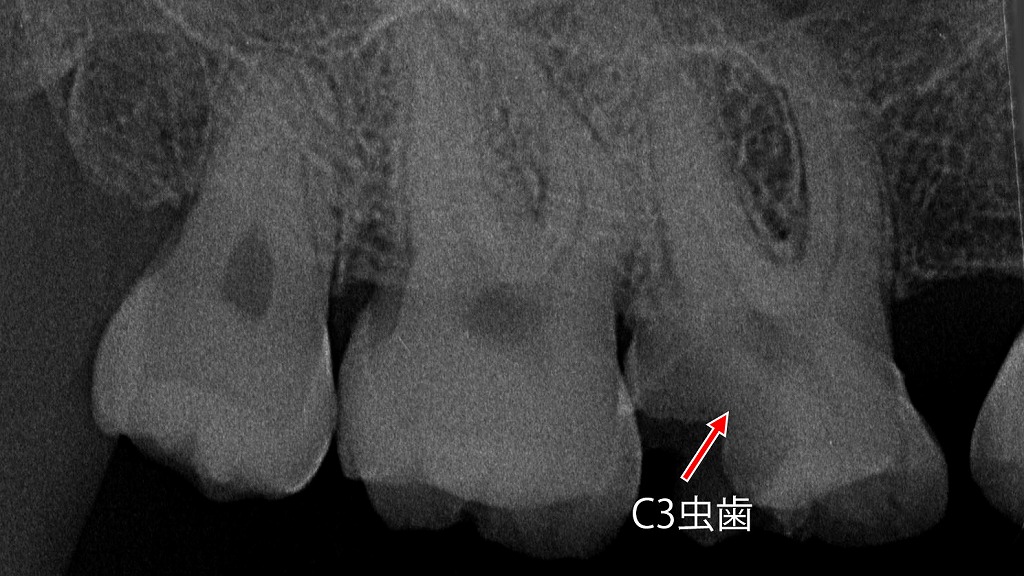

冷たいものがしみる理由 ― C3虫歯から根管治療に至ったケース

冷たいものがしみる原因は、虫歯がC3まで進行し神経に近づいたためです。術前のレントゲンでは深い虫歯が確認され、神経の炎症が疑われました。根管治療により感染した神経を除去し、歯の根の中を消毒・密封することで、痛みやしみる症状の原因を取り除き、歯を抜かずに保存しています。